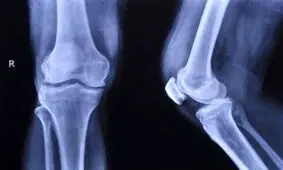

استخوان یکی از اصلیترین اعضای بدن است و تقویت آن در دوران کودکی باعث سلامتی و حتی تناسب اندام در بزرگسالی میشود.

استخوان ضعیف دردسرساز است به حدی که به ناتوانی یا حتی مرگ زودرس فرد منجر میشود.

کلسیم یکی از عناصر کلیدی برای حفظ سلامت و استحکام استخوان ها است.